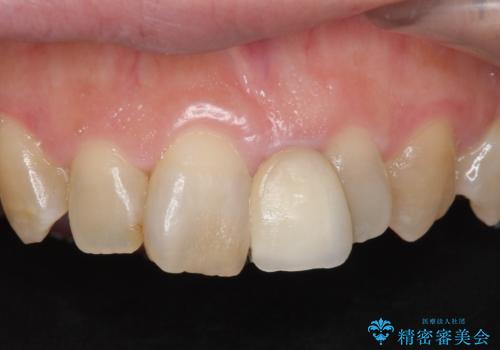

- 前歯の歯並びや色が気になるといらっしゃった方の症例です。

前歯4本をオールセラミッククラウンで補綴することで、歯の並びや色の改善を行いました。

今回用いたオールセラミッククラウンはジルコニアフレームという白い素材の上にセラミックを盛っているため、審美性が非常に高いのが特徴です。